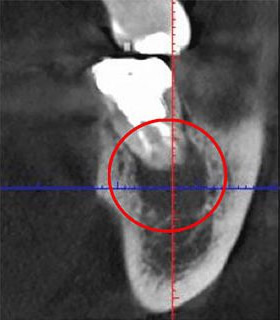

次の比較画像は、同じ歯をCTとレントゲンで撮影したものです。

左の画像がCT、右がレントゲンです。

左のCTでは黒い影が見えます。この黒い影は、歯の根の炎症です。右のレントゲンには写っていません。レントゲンだけの検査の場合、この炎症は見逃されてしまうということです。

CTを使うことで、初期の炎症も見逃さずに、適切な診断ができます。